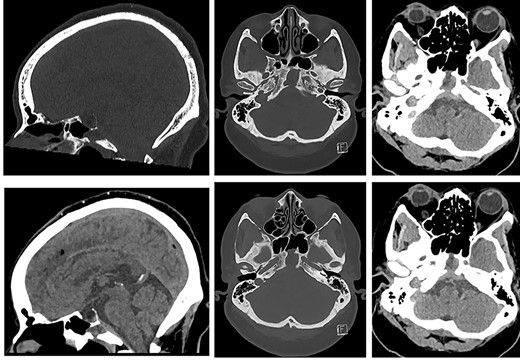

It was therefore decided that prolonged intravenous antibiotic therapy would be needed. She was discharged home with Ceftriaxone intravenously 4 g once daily (for central nervous system cover of S. aureus) and Ciprofloxacin orally 750 mg twice daily (to cover Proteus and Morganella). An MR head after 6 weeks (Fig. 6) showed reduced fluid in the sphenoid sinuses, but slightly increased dural thickening. In view of this, and the patient’s ongoing headache, the antibiotics were continued.

![MRI of the head and orbits (top row: sagittal T2WI and sagittal T1WI post-contrast; bottom row: axial T1WI post-contrast at two levels [cranial to caudal]) showing increased retroclival dural thickening; the volume of fluid and mucosal thickening in the sphenoidal sinuses and clival cavity is reduced.](https://oupdevcdn.silverchair-staging.com/oup/backfile/Content_public/Journal/jscr/2022/1/10.1093_jscr_rjab607/1/m_rjab607f6.jpeg?Expires=1778768511&Signature=DRMo2hG2LiCZ7K6GKQsaTAHgKj3zVLlJn-v3U2vGZwVnThOh6ydaWxJ8h-y9Ivmds2uOKtveqC393E~atmVFuR8BEvsXAfgVQy7-eJgfPFMi5pWz4dNGpaHt3vBrFc-wRCyUCP7Xm5W~c3oePhsqRHbMFpFdpjI5l~QGbrs9MJR665FuTYJdoBt0uZIq7QZRQGvWeYvRRnWNOmTMeOiE8hVX7gos3hzn5~Mecq0q8sAUR61v7PuAWbzq5HcF5lL4~NgMomVVM19AP5NAcDpRAGQoozPuZ4K8sE2e8QqJp0DUpv81X6FOOST1htriKH0DADdUcuOimBuy7CJmu1sIUA__&Key-Pair-Id=APKAIYYTVHKX7JZB5EAA)

MRI of the head and orbits (top row: sagittal T2WI and sagittal T1WI post-contrast; bottom row: axial T1WI post-contrast at two levels [cranial to caudal]) showing increased retroclival dural thickening; the volume of fluid and mucosal thickening in the sphenoidal sinuses and clival cavity is reduced.